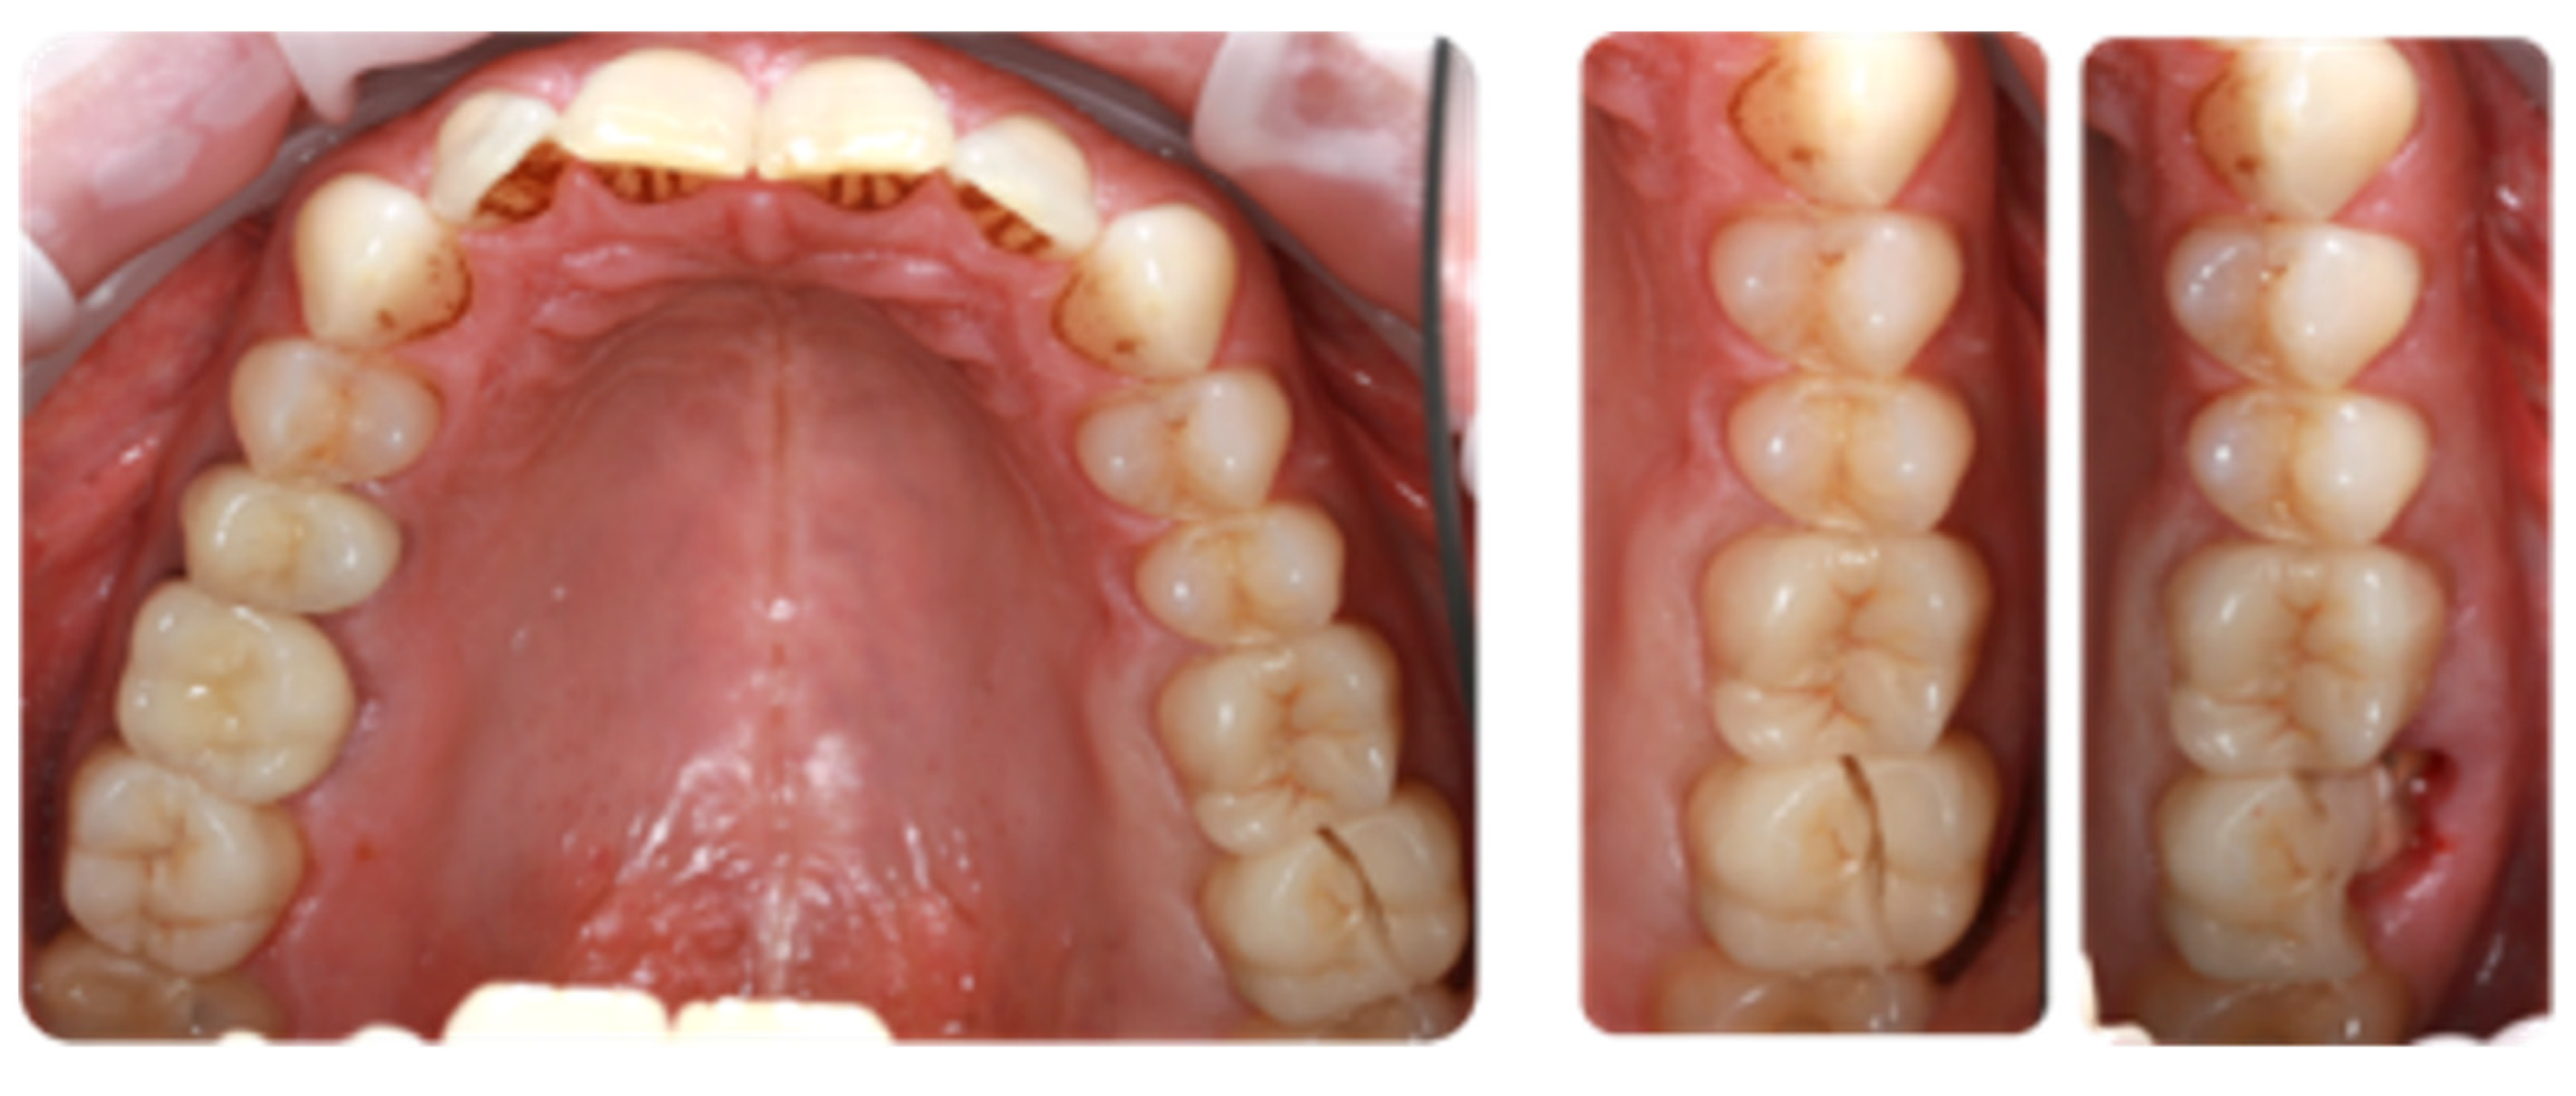

All clinical procedures were performed by a single investigator (A.G.). The clinical assessment of the monitored parameters was carried out by two researchers (A.G. and N.N.), using Optagate (IvoclarVivadent, Schaan, Liechtenstein), air, a probe for caries diagnostics (Dental Explorer 23/17A Double Ended), and magnification (x4.0 Dental microscope, Carl Zeiss, Oberkochen, Germany) for marginal zone analysis and the presence of cracks and fractures (adhesive or cohesive). We also assessed and recorded factors such as fracture incidence, esthetic changes, carious process, staining in the cementum area, soft tissue tolerance, and patient discomfort. Esthetic parameters were evaluated clinically in terms of color match and surface roughness. Indirect ceramic restorations were graded as perfect, clinically acceptable, or clinically unacceptable in each grading category. We confirm that we have read the Helsinki Declaration and followed the guidelines for this investigation.

The 10-year long-term follow-up shows an entrainment of the “Bravo” grade in all USPHS criteria studied. There was an increase in Criteria 2 to 6 over the second follow-up period (Table 5). The “Charlie” rate remained unchanged at Criterion 5 over the 5-year evaluation period (4.54%). In Criterion 6, an increase was found for the 10-year follow-up compared to the 5-year follow-up, from 2.27% to 4.54% (Table 5). Data analysis identified the first occurrence of a grade of “Bravo” in Criteria 1, 4, and 7 over the 10-year follow-up period; the same for both criteria was 4.55% (Table 5). Four of the all-studied restorations (n = 86) had to be replaced at year 5 follow-up because of fracture (failure rate 4.65%; Kaplan–Maier). There are no restorations with bulky, cohesive fractures. Group II demonstrated a satisfactory success rate in terms of color matching and secondary carious lesions during the 5-year follow-up period (Table 5, Figure 1).

Back in 2000, Hayashi M. et al. evaluated the quality of feldspar ceramics after eight years in vivo. Durability was observed in 80% of feldspar ceramic inlay restorations after eight years (Kaplan–Meier method), although at six-year reporting, it was 92%, which differs from the results obtained in the present study—95.35% for both 5-year and 10-year follow-up. A change was observed from the 5-year period to the 10-year period, where the “Charlie” rate increased from 1.16% to 3.49%, or from one clinical case to three of the total number of followed cases (n = 86) (Table 2). The results show that the “Charlie” grade under criterion 6—“Marginal integrity”—fracture of the restoration or missing part or the entire obturation, leads to the replacement of the ceramic restoration with a new one three times in a 5-year period (from the 5th to the 10th year), but the increase in durability is related to the increase in the resistance of the materials and the increase in their strength (Figure 2 and Figure 3). Hayashi M. et al.’s follow-up revealed marginal fractures in 11 restorations (22%), with 5 (11%) experiencing volume fractures for the first time in the previous two years. We observed recurrent caries in 3 (7%) cases and marginal staining in 14 (31%). SEM evaluation revealed marginal microfractures in 77% of the restorations, wear in 36%, and edge wear in 74% at eight years. No significant difference was observed between molars and premolars [46]. One of the cases (#47) with cohesive fracture in the present clinical trial is presented in Figure 4A.

The results of the present study clearly show that the main problems are the interproximal contact and the destruction of the marginal integrity between the restoration and the tooth structures (Table 2).

One of the serious problems that has remained for decades is still the impossibility of maximum adaptation in the marginal approximal areas where the level is below or at that of the interdental soft tissues. The clinical study included a tooth that we have been following for more than 10 years, with a radiographically diagnosed cleft at the distal gingival base. Due to the patient’s lack of symptoms, the case is being followed for longer, but the change in the indirect restoration is also planned (Figure 4B).